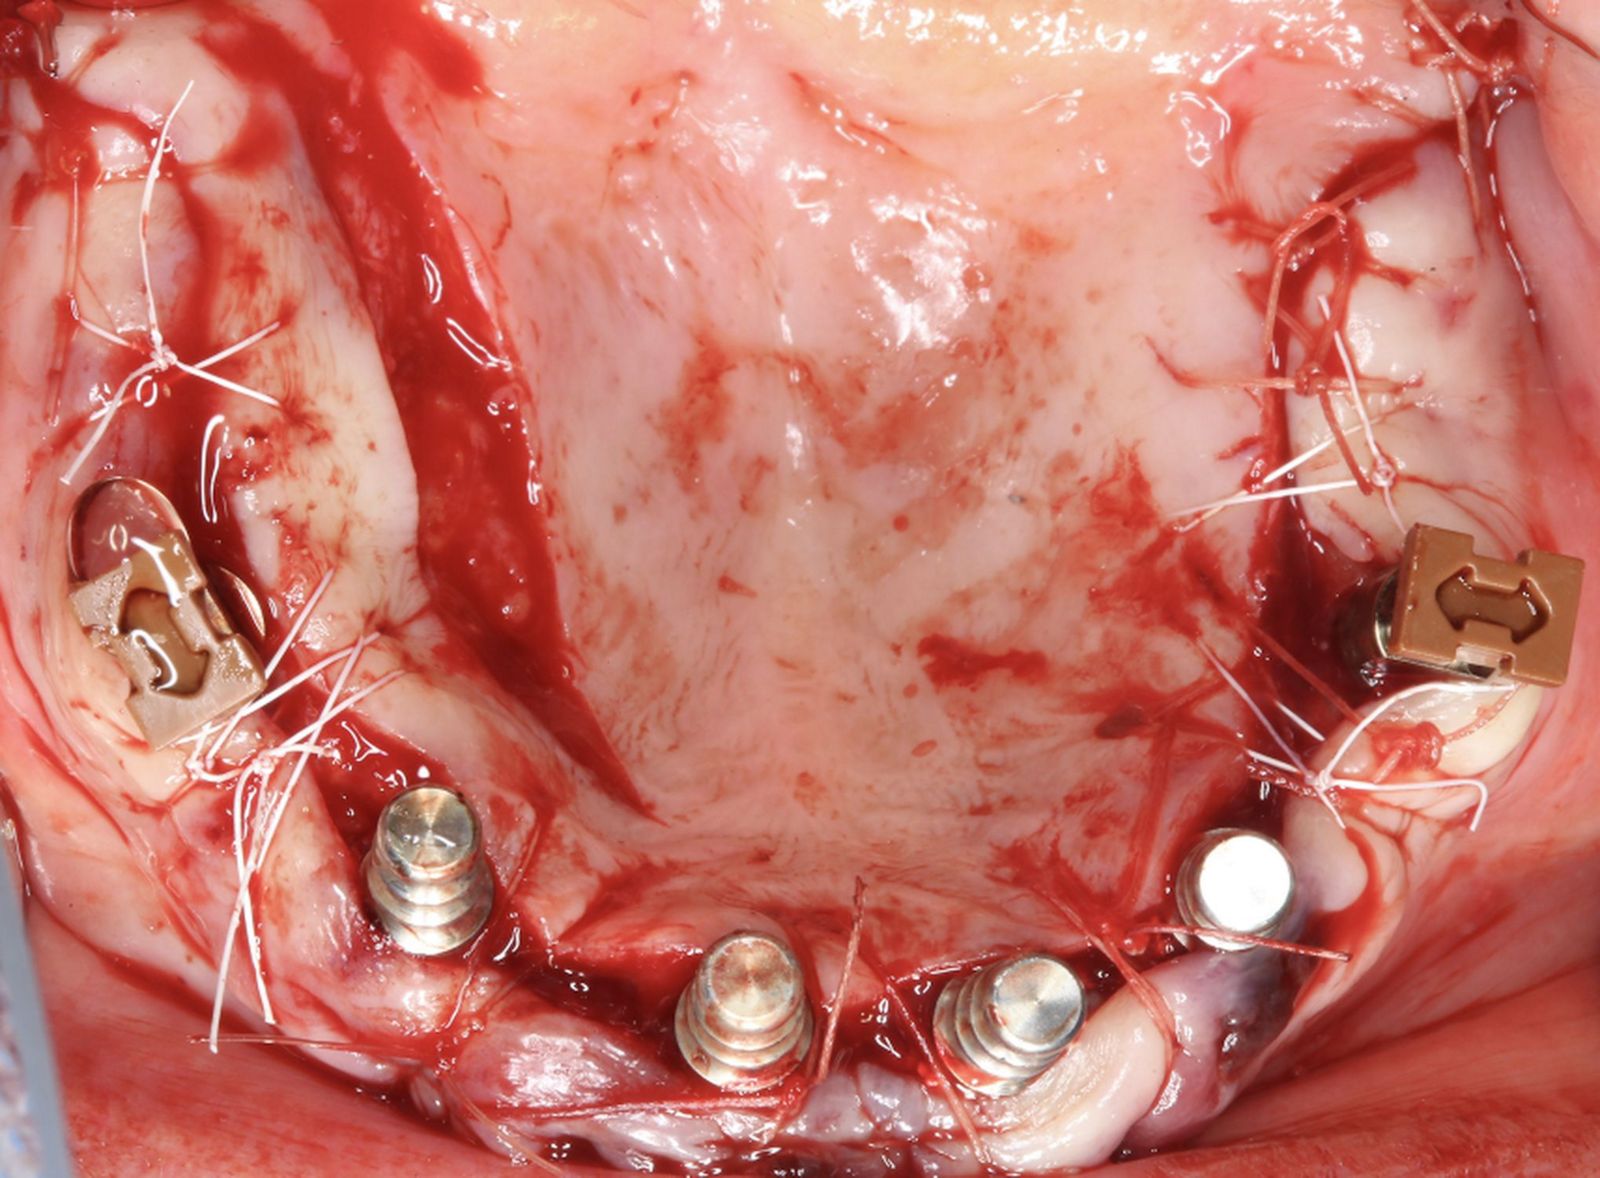

Встановлено усі імплантати на верхній щелепі